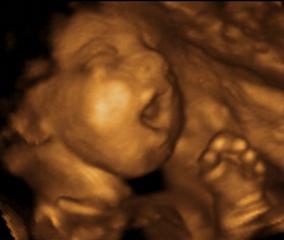

“I wish I would have had the opportunity to see an ultrasound, or information about fetal development, before my abortion at age 16. There are no words to describe the amount of pain, guilt, and trauma I experienced when I saw pictures of fetal development two years later. I was horrified that the “products of conception” and “tissue” I had “removed from my uterus” had had precious little hands and feet, and a beating heart. I felt like a monster. And I felt betrayed by the medical professionals I had trusted.” Lisa Skowron from San Antonio